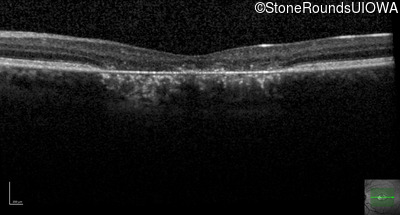

This 22 year old man had macular abnormalities noted incidentally at a routine eye exam at age 19. Since then, he has experienced a gradual loss of acuity particularly in the left eye.